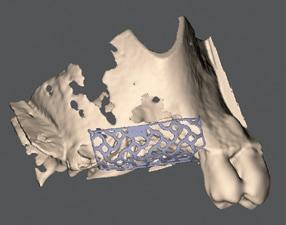

Eine weitere Möglichkeit, insbesondere bei komplexen dreidimensionalen Defekten, welche eine notwendige Lage- und Volumenstabilität für das partikuläre Transplantat auch über größere Distanzen ideal erfüllt, ist die Anwendung eines Titangitters. Das Verfahren wurde erstmals in der Rekonstruktionschirurgie nach Tumoren und Traumata 1969 von Boyne beschrieben [2] und findet seit 1996 Anwendung in der präimplantologischen Augmentationschirurgie [18]. Die früher noch intraoperativ angepassten Titangitter führen in der Literaturübersicht von Rasia dal Polo zu einem durchschnittlichen Knochengewinn von fast 5 mm vertikal und 4 mm horizontal und zeigen planbare Ergebnisse mit geringen Komplikationsraten [11]. Heute, mit Fortschreiten der Digitalisierung, können patientenindividualisierte Gitter hergestellt werden (Yxoss CBR®, Geistlich). Hierfür werden die DVToder CT-Daten des Defekts zur individuellen Konstruktion des Meshs verwendet, welches dann mit dem selektiven Laserschmelzverfahren Schicht für Schicht dreidimensional gedruckt wird. Das Augmentationsmaterial wird durch die Volumenstütze somit optimal im Defektbereich stabilisiert und die Augmentation kann durch ein Backward-Planning im Bereich der prothetischen Position erfolgen. Diese präoperative Planung und Herstellung reduziert die OP-Dauer im Vergleich zur intraoperativen Herstellung um ca. 30 Min. und ermöglicht aufgrund der passiven Lage des Titangitters eine wesentlich einfachere Fixation ohne bestehende Rückstellkräfte oder scharfe Kanten. Durch die bessere Passform und die geringere OP-Dauer wird im Vergleich zu herkömmlichen Titangittern die Wunddehiszenz als Hauptkomplikation dieser Augmentation deutlich gesenkt [15].

Nach einer Abheilzeit von 10 Wochen wurde im Rahmen der präimplantologischen Diagnostik aufgrund der Komplexität der Defektsituation im 1. Quadranten regio 16 und 17 neben der klinischen Untersuchung eine DVT-Aufnahme angefertigt. Es zeigte sich ein transversaler und vertikaler Knochendefekt mit einer Restknochenhöhe von teilweise nur 1 mm. Zu beachten war auch die Höhe des Knochenlagers, das sich teilweise auf Höhe des Apex des Nachbarzahnes 15 befand (Abb. 1a und b). Dieser dreidimensionale Defekt sollte durch einen externen Sinuslift nach kranial sowie eine ventrale horizontale auflagernde Augmentation ausgeglichen werden. Hierfür wurde mit dem DICOM-Datensatz der DVT-Aufnahme ein virtuelles Modell hergestellt, welches die Planungsgrundlage für das Augmentationsvolumen darstellte (Abb. 1c). Anhand dieser Daten und in Abstimmung mit dem Behandler stellte die ReOss GmbH ein patientenindividuell gedrucktes Titangitter für die Augmentation her.